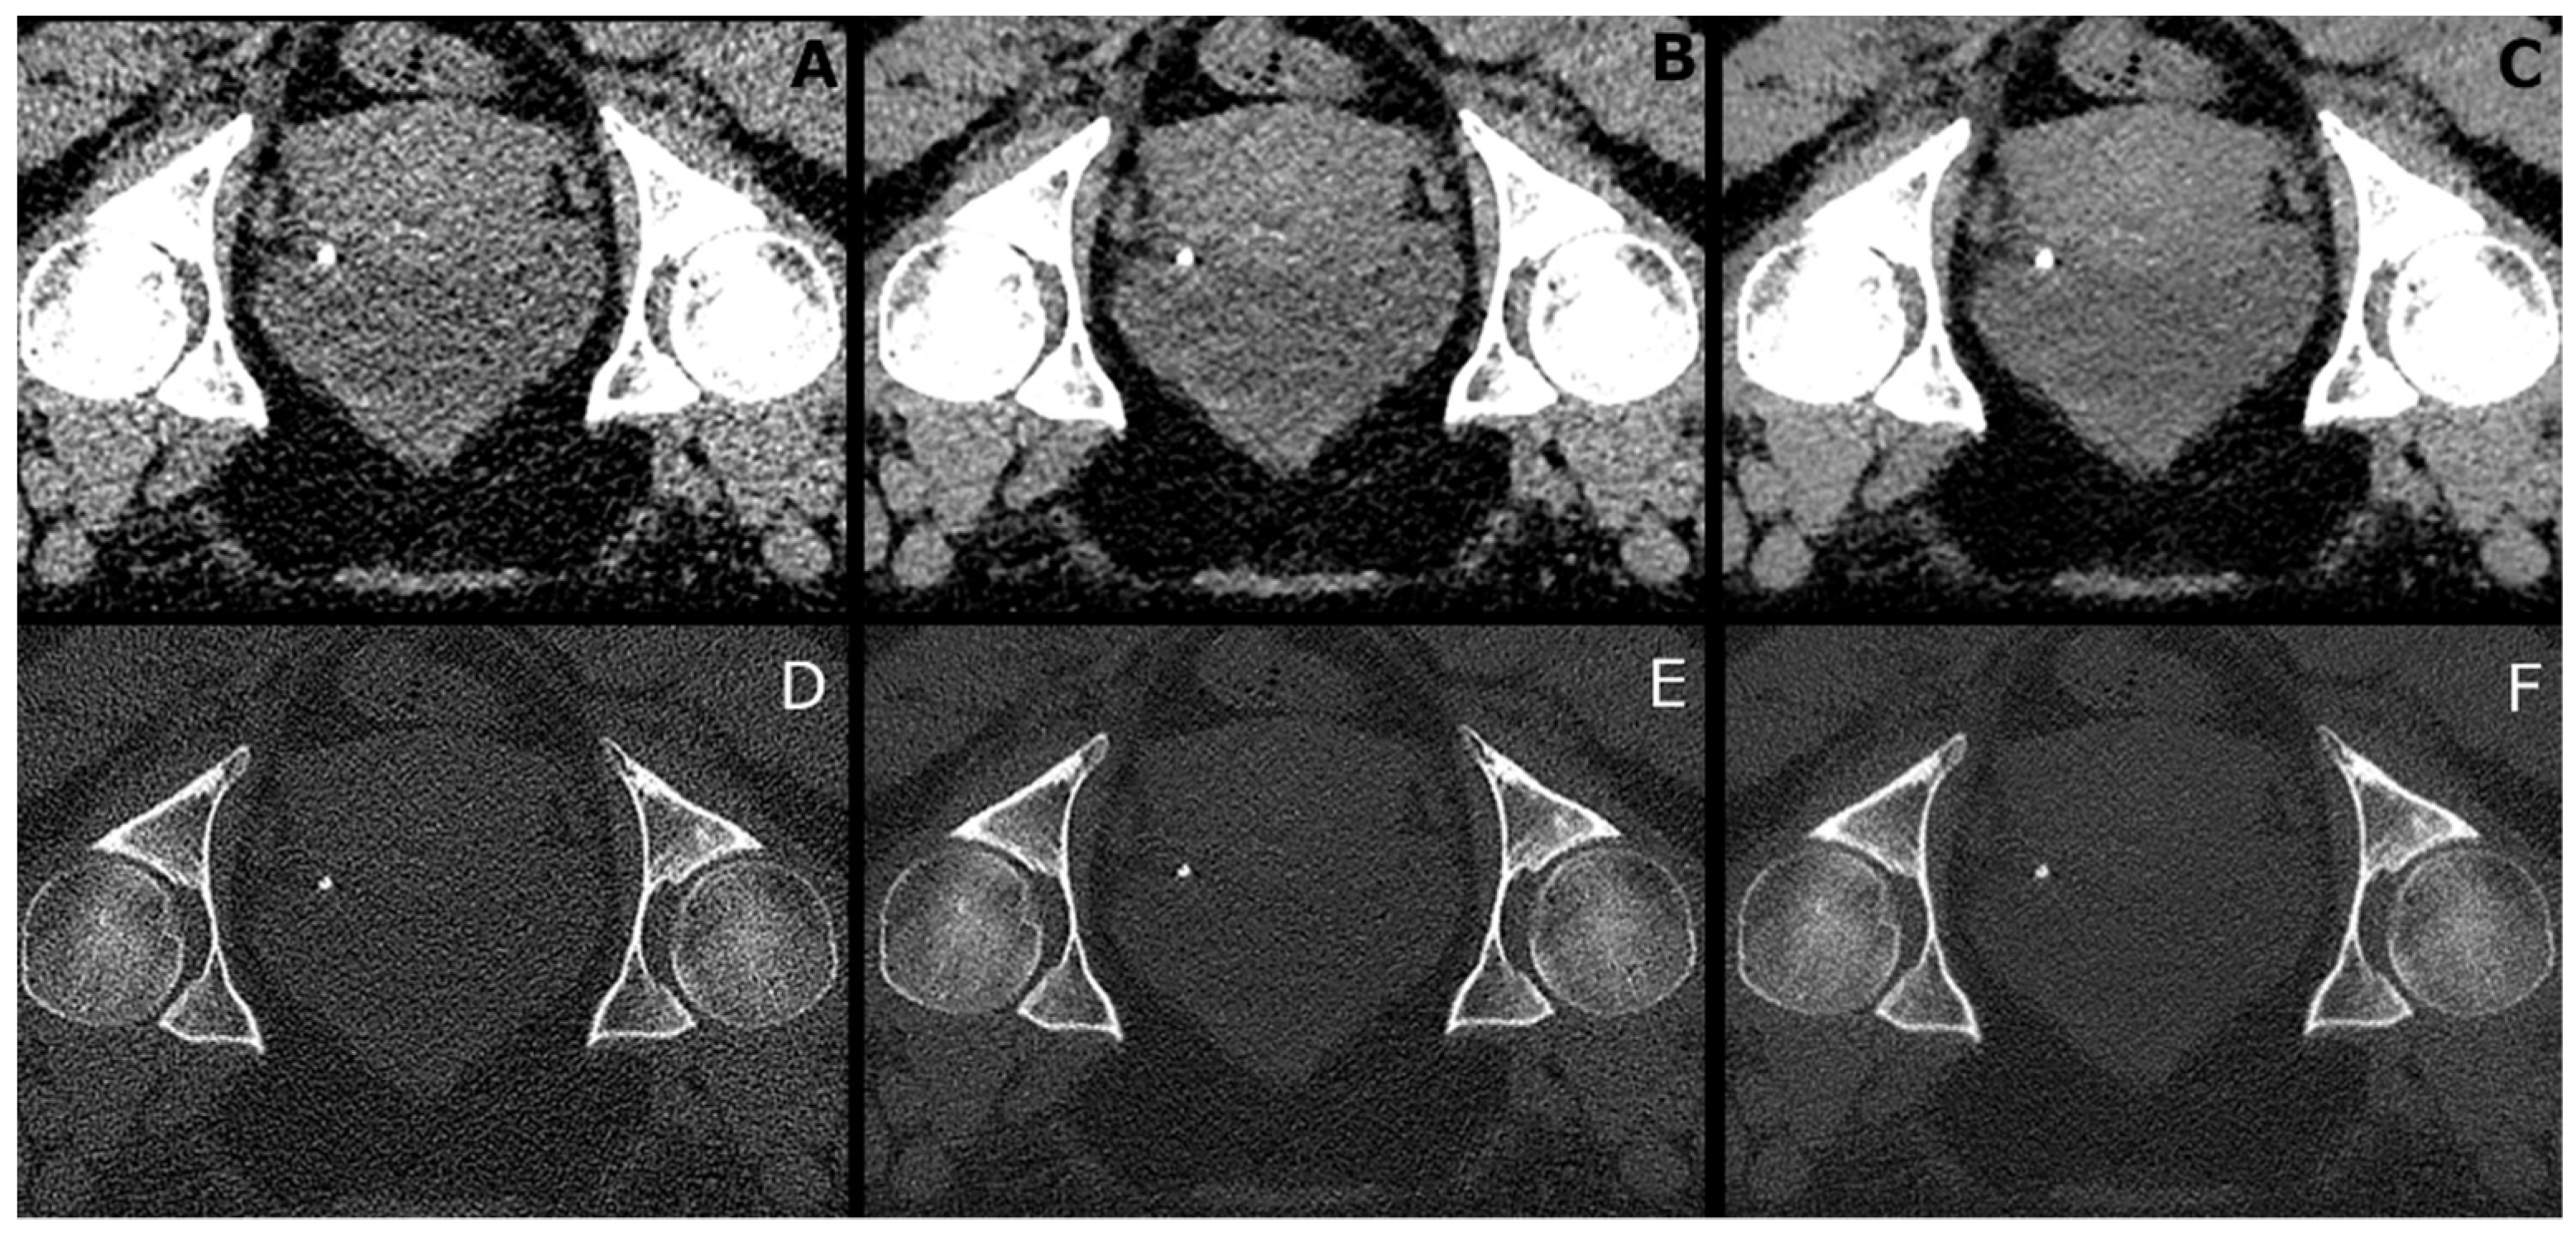

- (a)

- B30f: Filtered back-projection with a B30f kernel for soft tissue presentation.

- (b)

- B70f: Filtered back-projection with a B70f kernel for bone or lung presentation.

- (c)

- I30f: Iterative reconstruction (SAFIRE (Siemens Healthineers, Forchheim, Germany)) with an I30f kernel for soft tissue presentation.

- (d)

- I70f: Iterative reconstruction (SAFIRE (Siemens Healthineers, Forchheim, Germany)) with an I70f kernel for bone or lung presentation.

- (e)

- P30f: PixelShine (AlgoMedica), version 1.2.104, using the reconstructed images of (a) with the parameters P214A8S.

- (f)

- P70f: PixelShine (AlgoMedica), version 1.2.104, using the reconstructed images of (b) with the parameters PB14A4L2.

3.5. CT Values and Image Noise in Tissues and Air

3.6. SNR and CNR